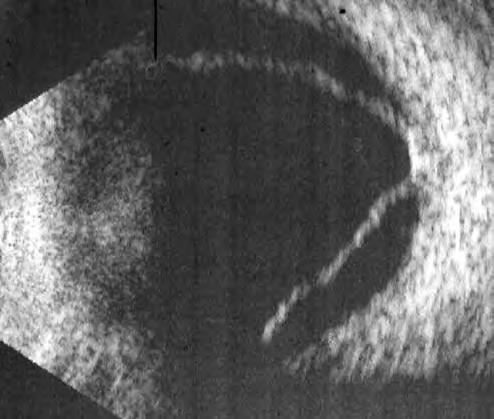

放上前置镜,我之前的想法得到印证:灰白色的视网膜隆起,漂浮在玻璃体腔里,下方可以看到一个大裂孔,裂孔边缘已经翻转,有了增值条索。

这是一个孔源性视网膜脱离的病人,且脱离的时间已经非常久,他的白内障、低眼压、葡萄膜炎表现都与陈旧性视网膜脱离相关。针对视网膜脱离的患者来说,如果不能早发现早治疗,视网膜脱离时间太长,视网膜将会丧失功能,预后会很差。